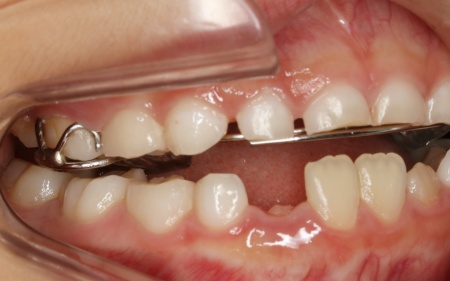

9歳女の子 反対咬合を顎の成長を利用した矯正装置を用いて改善した症例

治療後

お子様の成長に合わせて慎重に治療を進めることで、無理のない自然な形で歯並びと噛み合わせを改善することができました。